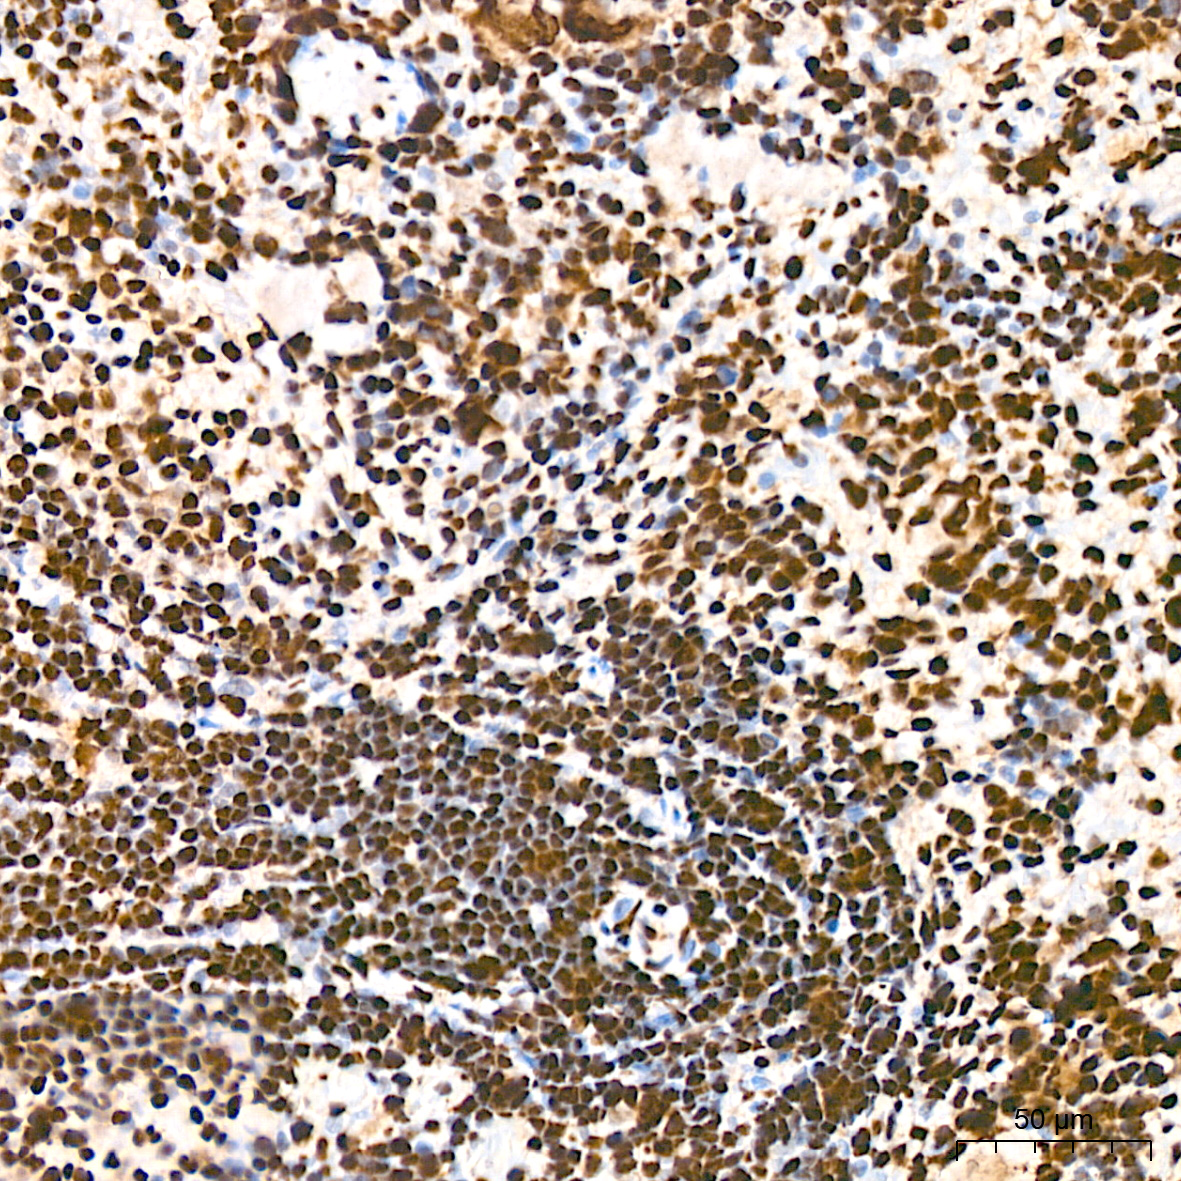

癌症